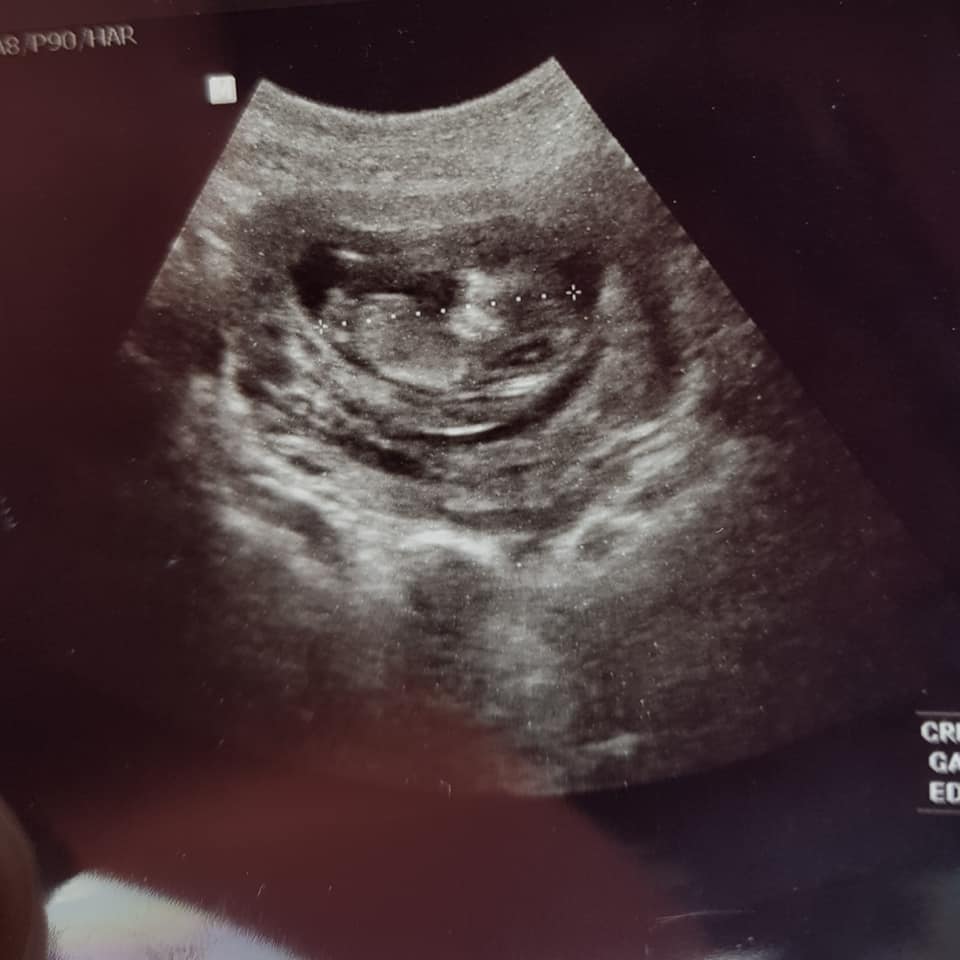

Scan done at 12weeks1day. I think it looks pretty obvious but want confirmation. We have 3 girls already![]()

It's too early for me to guess - why do you think it's obvious?? If you think it's a girl because you don't see anything yet, it is very very common for babies who look like girls at 12 weeks 1 day to actually be boys.

I would give a VERY tentative blue lean but please don't get your hopes up or paint the nursery yet because the baby is curled up, it's early, and the photos are grainy.!!! Questions??

An early boy guess from me too, my fingers are crossed for you.

Just back to say i got my NIPT result back and it's a healthy BOY